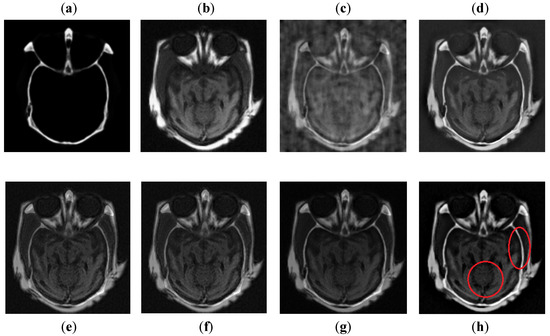

It can be seen in Figure 10 that DCT has poor results with more artifacts. The DWT method also has artifacts and pixel discontinuities due to limited directional information. The image obtained by NSST-SF-PCNN has better visual effects, but it has uneven illumination, and due to that, the fused image lost some vital information. The CSR and CNN methods resemble each other, but the contrast of CNN is better than CSR. Both methods acquire good visual results and have good image contrast, but some edges and boundaries are not vivid. The proposed method again shows its supremacy by producing output image with vivid contrast and high resolution. Additionally, it can be depicted in red boxed to capture smooth edges and contours more precisely.

Figure 10. Data-4: (a) CT image, (b) MRI image, (c) DCT, (d) DWT, (e) NSST-SFT-PCNN, (f) CSR, (g) CNN, (h) and Proposed.